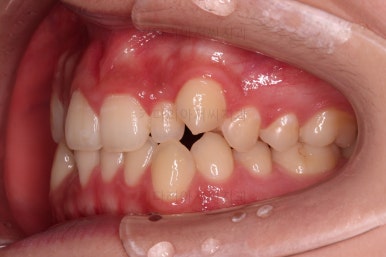

마찬가지로 초진 시 입안의 모습인데요.

위아래 앞니가 삐뚤고, 송곳니는 덧니처럼 불룩 튀어나가 있네요.

위아래 앞니는 안으로 굽어 들어와 있는 옥니(뻐드렁니 반대) 양상이었고요.

그리고 마무리 때 디테일에 문제가 생길 수 있는 부분인데, 윗니 대문니(가장 중간 치아)와 송곳니 사이의 치아를 작은 앞니라고 하는데요.

이 작은 앞니가 가져야 될 크기보다 더 작은 양상이었습니다.

이런 치아를 왜소치라교 표현합니다.